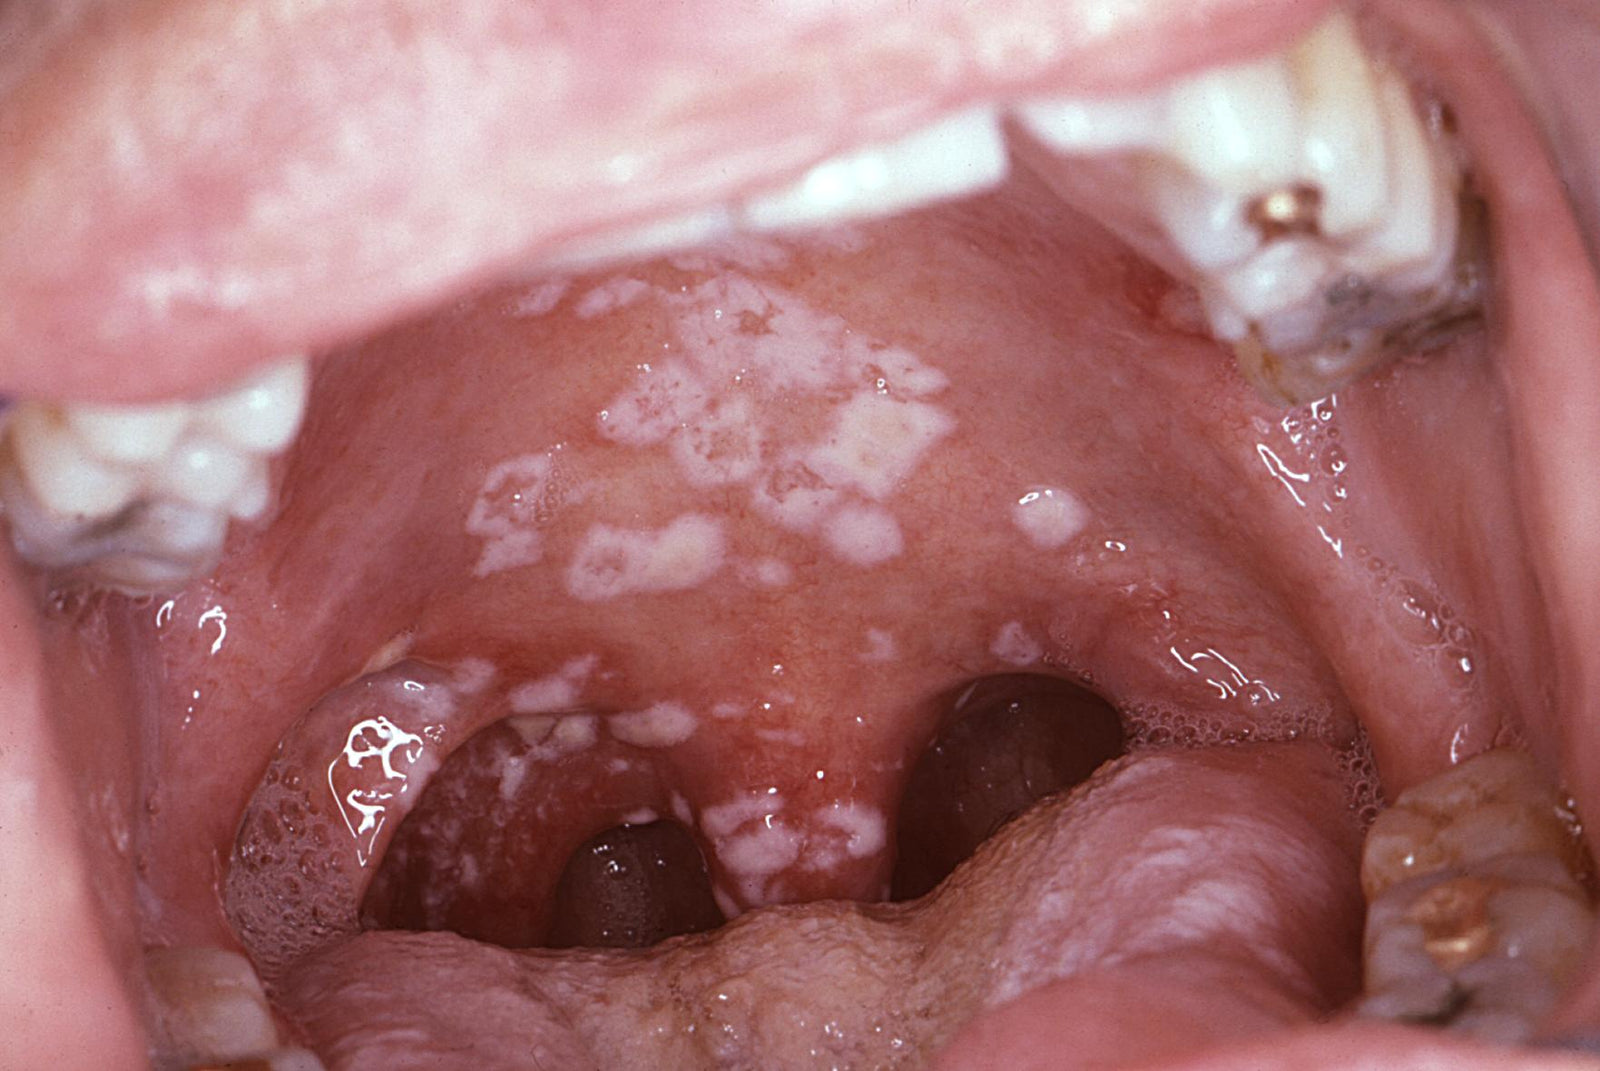

Candida is a type of yeast that is naturally found on various areas of the body, including the rectum, vagina and the mouth. Those with compromised immune systems are at risk for an overgrowth of yeast in the mouth called Oropharyngeal Candidiasis, or more commonly known as Oral Thrush. It is a common opportunistic infection in cancer patients.

Candidosis can be a serious complication for immunocompromised patients. Advanced cases can spread to other parts of the body, such as the digestive tract, lungs, and liver. Thrush infections that spread into the bloodstream can be fatal. For those at high risk, regular use of products containing 100% xylitol may assist in the prevention and management of Oral Candidiasis.